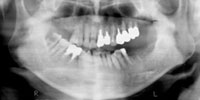

パノラマレントゲン写真

吉本歯科医院では、口内写真とパノラマレントゲンを撮影し、まずは顎の骨の状態まで詳しく確認しました。

CT画像で見ると骨の厚みが1、2ミリしかなく、通常の10ミリのインプラントを入れればシミュレーションのように鼻の空洞に突き抜けてしまうばかりでなく、強い力で噛んだ時に骨折する恐れがあります。.